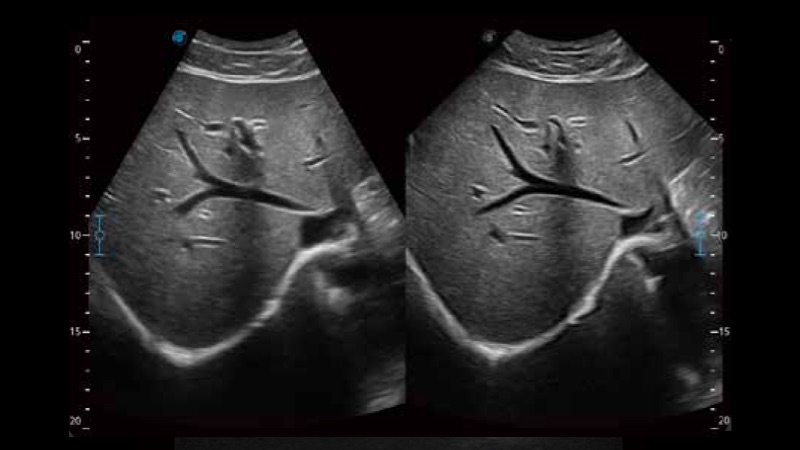

扩展成像技术

凸阵、线阵和相控阵探头进行实时扫描时,开启扩展成像模式,可以扩展超声图像视野,以便更完整地查看大的病灶或组织器官的解剖结构。

实时宽景成像技术

通过彩色血流和实时宽景相结合,可观察到完整的动静脉血流,方便医生检查。实时扫查过程中,如有任何操作失误也可以很容易地进行回扫擦除,而不会中断扫查。